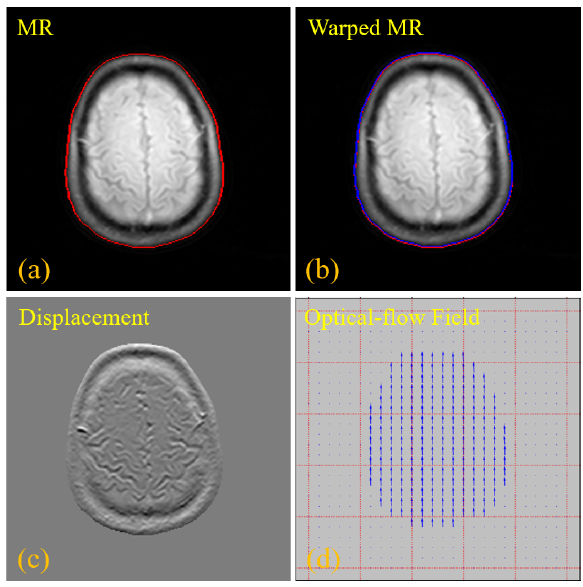

IEEE TMI| 深圳先进院开发PET/MR成像新技术

团队提出了利用光流网络将两者对齐,并且将光流网络嵌入到“端对端”网络模型中,无需额外标签进行监督学习

近日,beat365在线体育app 劳特伯生物医学成像研究中心胡战利研究员团队与中山大学附属肿瘤医院樊卫主任团队以及上海联影医疗公司的“产研医合作成果”,以OIF-Net: An Optical Flow Registration-Based PET/MR Cross-Modal Interactive Fusion Network for Low-Count Brain PE...